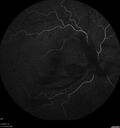

Severe Proliferative Diabetic Retinopathy and Good Vision

49 year old man with vision loss in the right eye for 2 weeks. VA 20/40 OD, 20/63 OS. DM x 15 years and HTN.